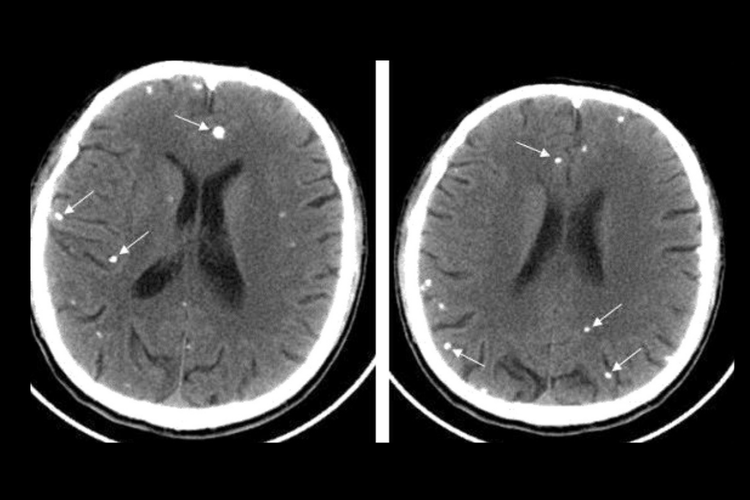

脑囊虫病的患者可出现头痛、癫痫发作、恶心、呕吐,还可出现眩晕、意识障碍、猝倒等颅内压增高的表现,当病灶位于大脑皮层时,可出现相应的运动、感觉、语言障碍,若病灶位于小脑还可能出现共济失调、眼球震颤等症状。病变部位通过CT检查可表现发现低密度影,其内可见小结节状等高密度影,为囊虫头节。